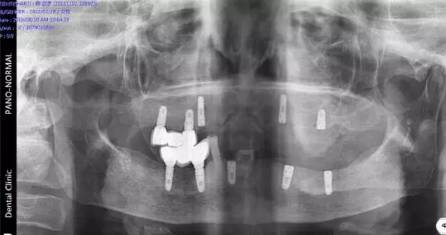

現(xiàn)場(chǎng)北京口腔醫(yī)學(xué)會(huì)專家、德國(guó)專家親自接診,經(jīng)過口腔CT確診,老人全口牙缺失,為其制定CHEESE德國(guó)激光種植技術(shù),8根牙根種出滿口好牙,不僅當(dāng)天種好,還省了錢。

(現(xiàn)場(chǎng)口腔CT拍片)